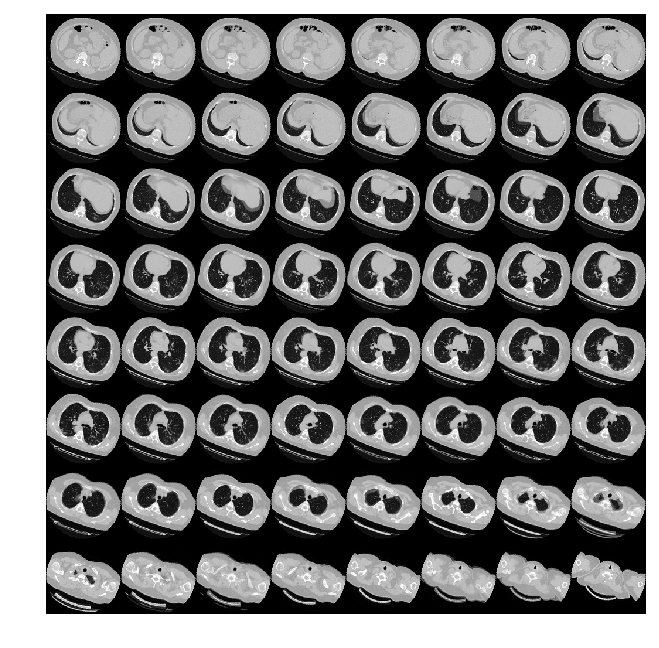

由于CT扫描有许多层切片,可视化多层切片。

def plot_slices(num_rows, num_columns, width, height, data):

plot_slices(8, 8, 128, 128, image[:, :, :64])